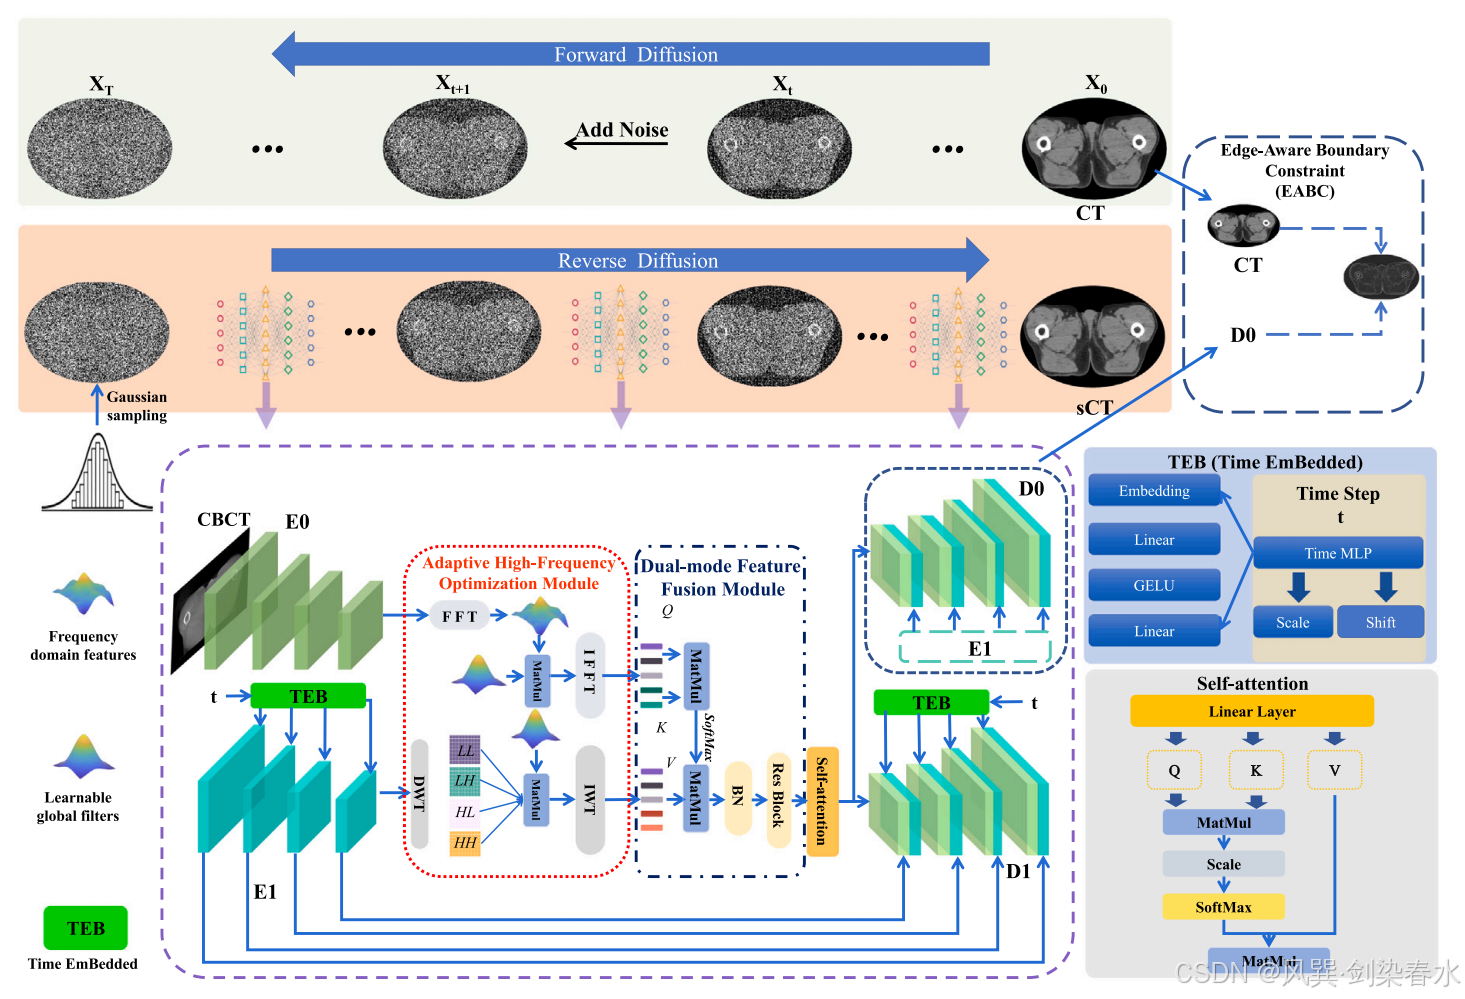

图 1 所示的方法采用了一个双分支的基于注意力机制的神经网络来对含噪 CT 图像进行去噪。该框架包含自适应高频优化(Adaptive High-Frequency Optimization, AHFO)模块、双模式特征融合(Dual-Mode Feature Fusion, DMFF)模块、时间嵌入(Time Embedded, TEB)模块以及一个边缘感知边界约束(Edge-Aware Boundary Constraint, EABC)损失函数,这些组件共同增强了传统的扩散范式,并提升了模型的特征提取能力。在去噪的同时,确保了与原始 CT 图像的一致性。

在逆向扩散步骤中,条件分支整合了 CBCT 图像,以指导主 CT 生成分支中当前含噪 CT 图像的恢复过程。此外,一个可学习的高频优化模块在合成 CT 和 CBCT 特征中优化高频成分,其中在 CBCT 分支中使用快速傅里叶变换(Fast Fourier Transform, FFT),而在 sCT 分支中使用小波变换(Wavelet Transform, WT)。随后,DMFF 模块利用自注意力机制,有效地融合了两个分支的特征。

在推理过程中,网络将从标准正态分布中采样的随机噪声与 CBCT 图像的输入相结合。这一过程最终生成了高质量的 sCT 图像,有效地实现了从 CBCT 到 sCT 的转换。总体而言,这种方法借助注意力机制、特征优化以及融合技术,对 CBCT 图像进行去噪,并生成高质量的 sCT 图像。

Figure 1 | 整体框架涵盖了正向和反向扩散过程: E1 和 D1 分别作为 sCT 生成主分支中的编码器和解码器;E0 用于引入额外的 CBCT 信息,而 D0 则是辅助解码器,用于引入边缘感知边界约束的额外损失函数;